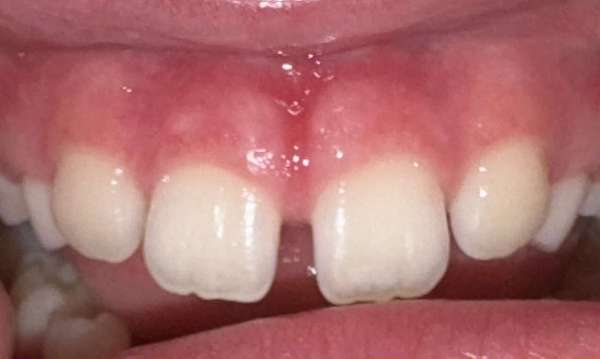

Frenectomy/Lip Release

CO2 Laser using to perform a frenectomy or lip release. The use of CO2 laser allows for treatment to completed very quickly with minimal tissue bleeding. Gingival tissues heal beautifully after laser treatment.